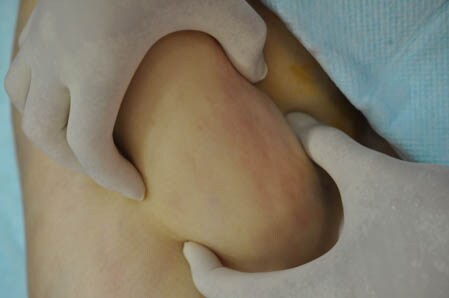

今回は太ももの脂肪吸引のご依頼をいただきましたので

その術中の模様を紹介したいと思います。

患者様のご期待にしっかりとお応えできた

術中になりました。